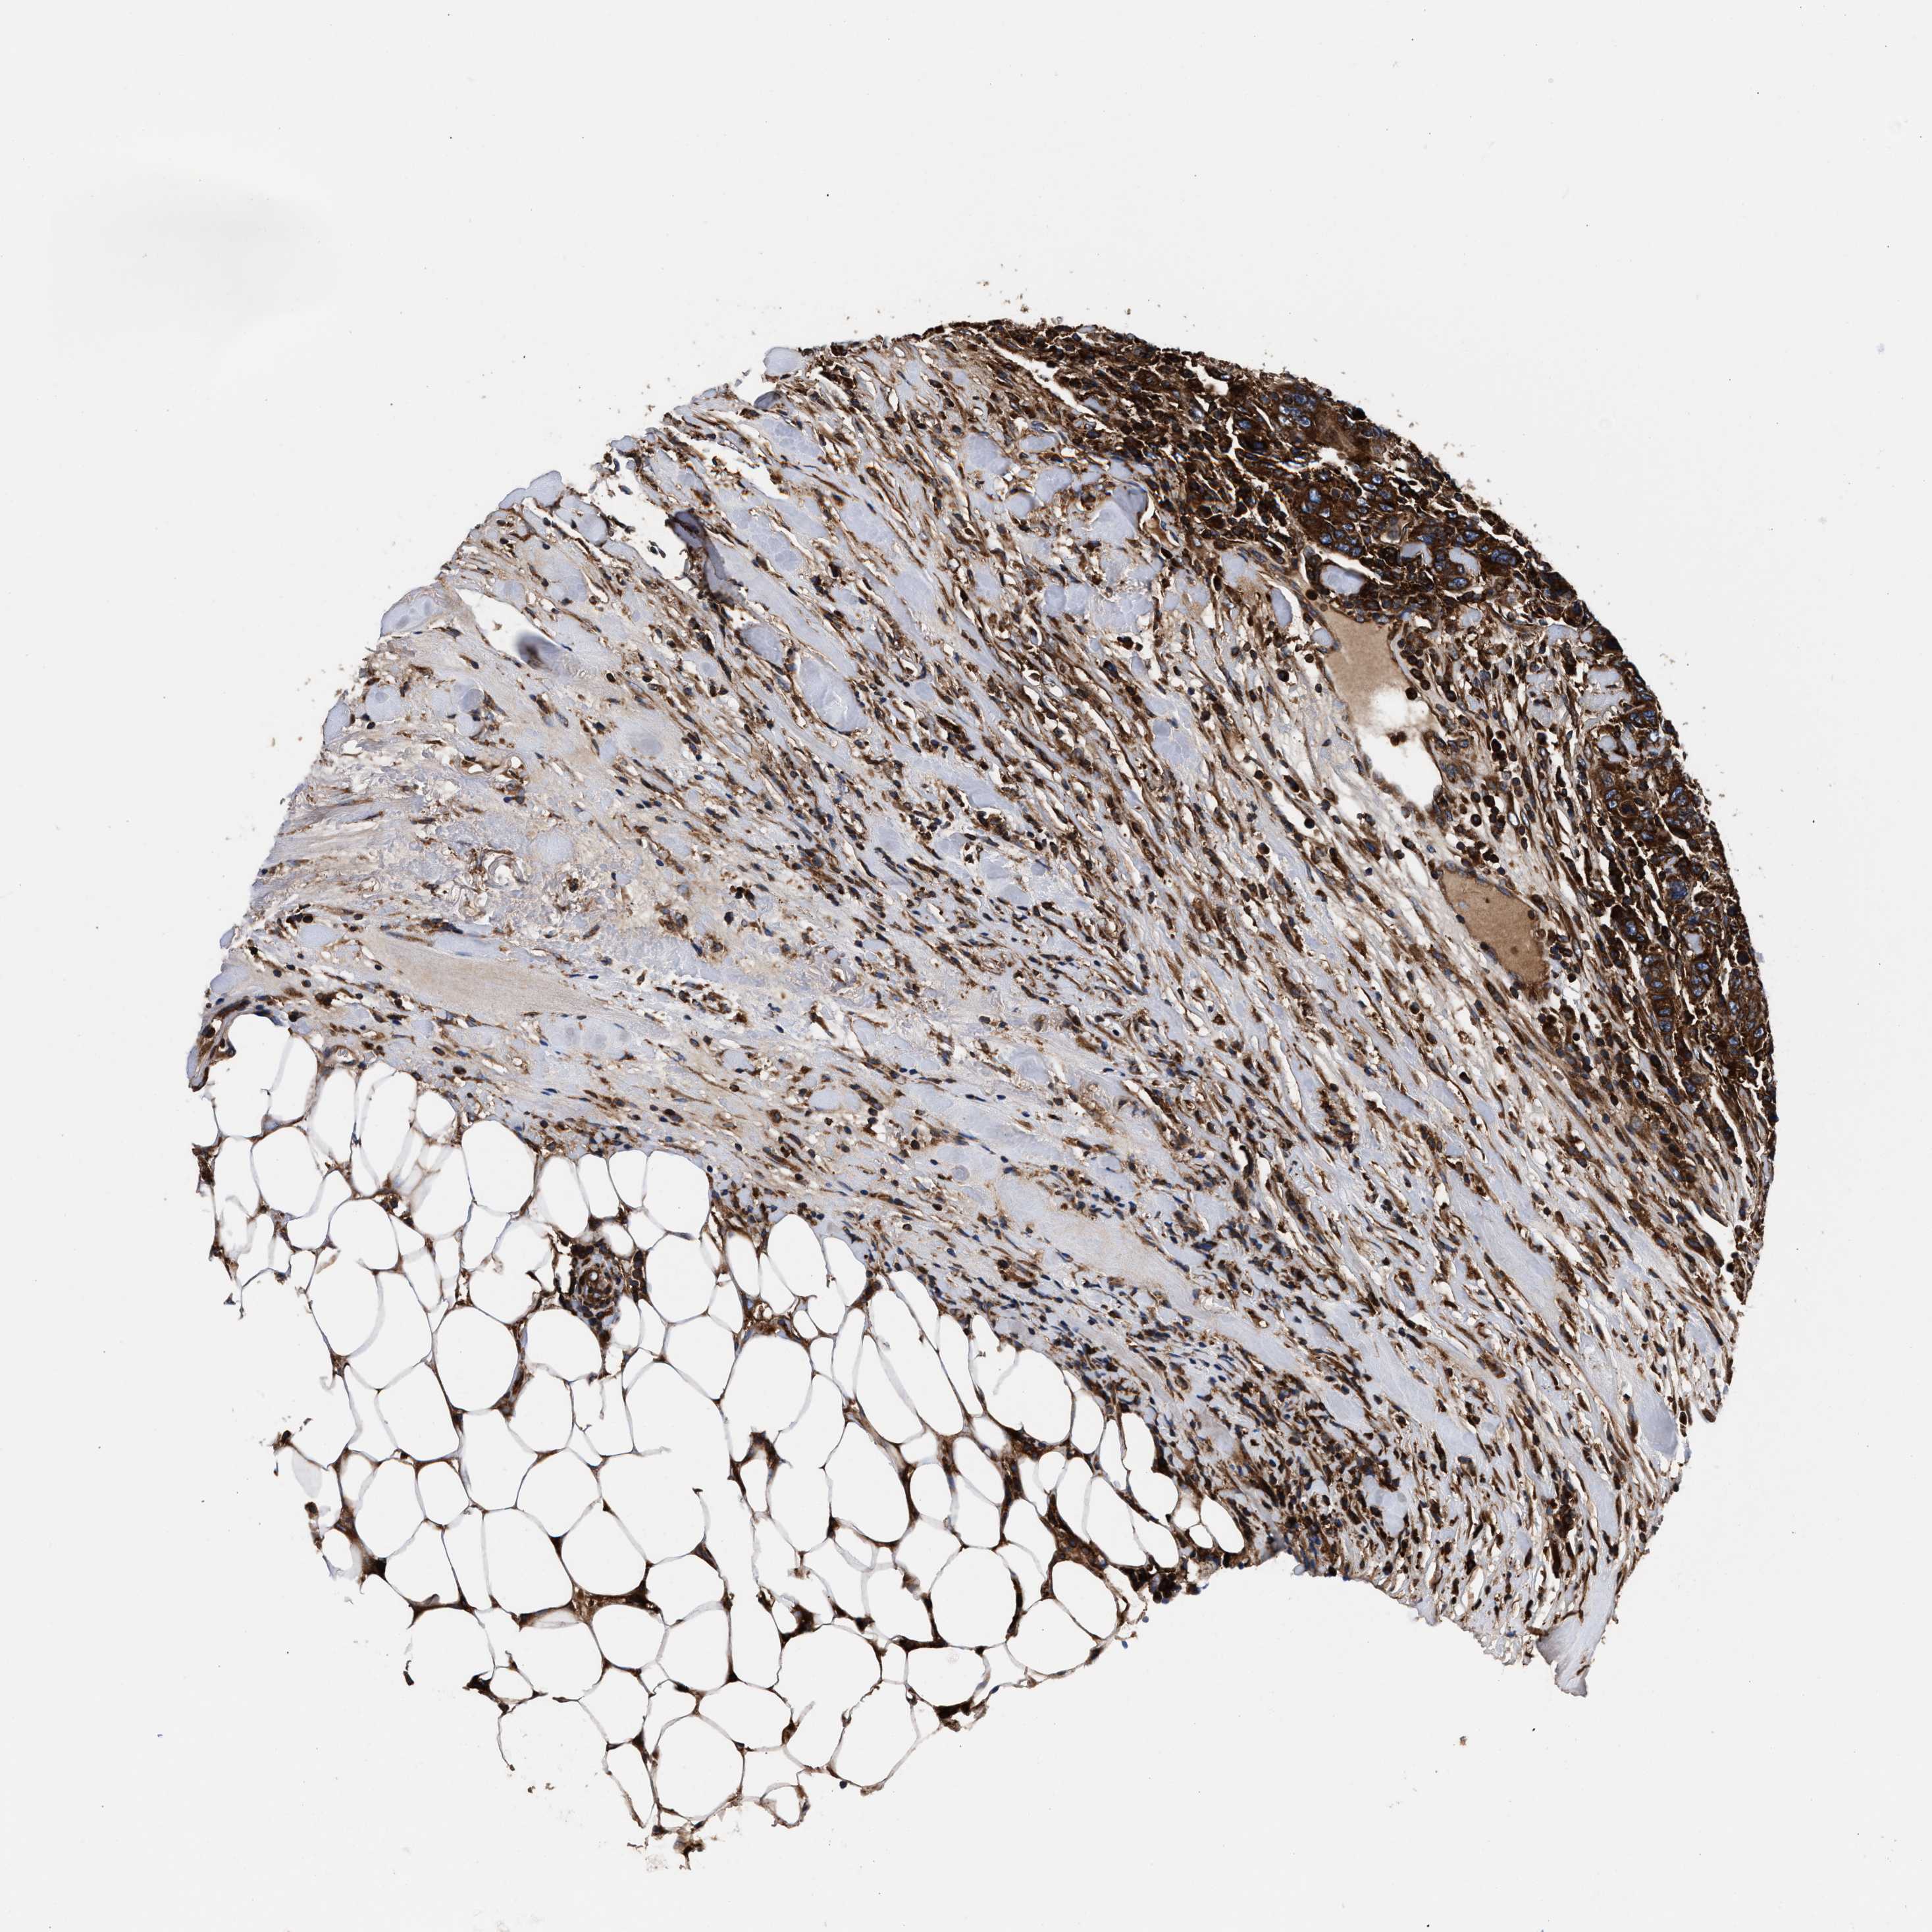

BRCA TCGA BRCA VALIDATION PROTEIN EXPRESSION

ANTIBODIES

AND

VALIDATION